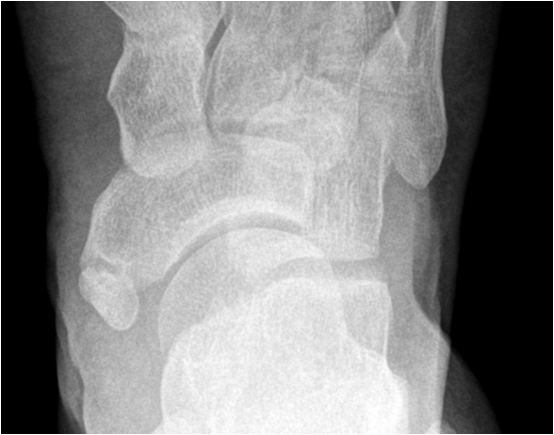

In the foot there is often involvement of the first metatarsal-phalangeal joint. In addition to joint space narrowing and subchondral sclerosis there is subchondral degenerative cyst formation and osteophyte formation along joint margins. Osteophytes are the sine qua non of osteoarthritis. In degenerative joint disease new bone formation is seen as a response or repair reaction. In inflammatory arthritis there usually is a destruction of bone and osteophytes are not seen.